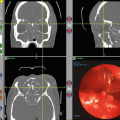

Fig. 20.1

Sprays have almost no sinus distribution to the paranasal sinuses prior to surgery. Mean sinus dispersion of radiographic contrast is extremely limited without surgical exposure of the sinus mucosa. This is particularly true of the frontal and sphenoid sinuses (Reprinted by permission of SAGE Publications, Harvey et al. [15])